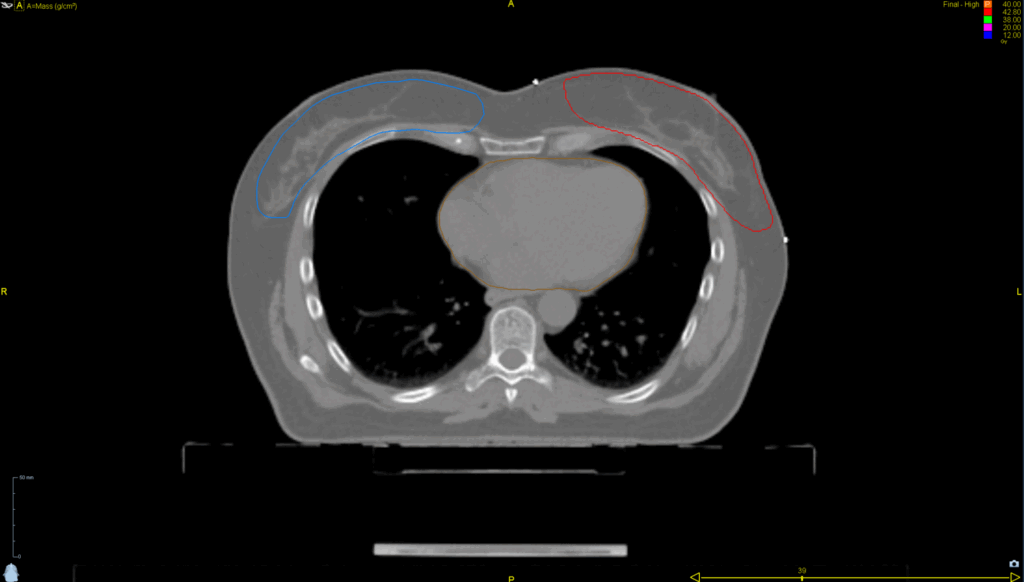

Left Whole Breast

Planning CT Images

PTV(s) Volume, Length

617 cc, 18 cm